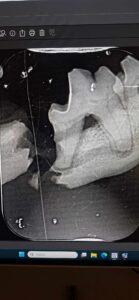

Rentgenas parodė ne tik perlūžusį bei sutrupintą žandikaulį, bet ir pakaušyje įstrigusį šratą, kurio įėjimo anga dar kraujavo… Kažkas šovė į seną mažą šuniuką, kas, galimai, turėjo įtakos įvykusiai nelaimei… Kam užkliuvo, kas toks beširdis?!

Sutvirtintas žandikaulis- ne paskutinė operacija. Dar, kai sugis, teks iš sutrupėjusios apatinio žandikaulio dalies ištraukti dantų šaknų nuolaužas.